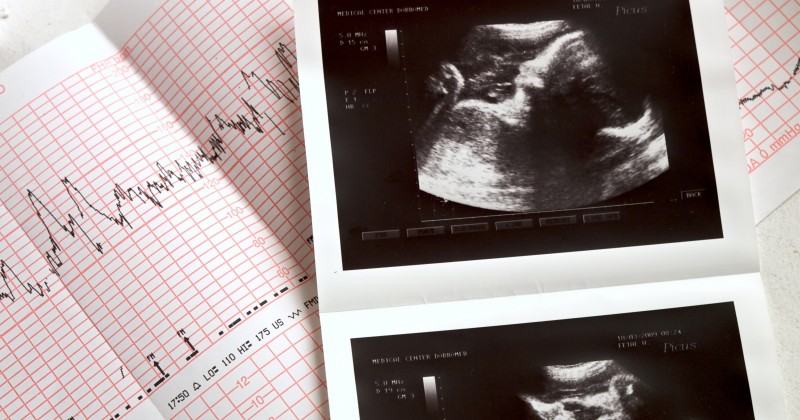

Five years ago my wife was five months pregnant. We were headed for an ultrasound to see the baby and have the doctors check to make sure everything was progressing nicely. We had done this three times before and were excited. All of our children were healthy and it never crossed our minds that the ultrasound would even take a long time. As we met with the doctor and ultrasound technician they referred to what they saw as “your child.” They must have said it 50x during the ultrasound as they referred to “your child's hand,” “your child’s heart,” etc.

Another doctor was brought into the room and for five minutes he stared at the baby's heart. The room was completely silent. I could tell my wife was becoming upset, but I was oblivious and thought she was overreacting. The doctor began to tell us that there was a tumor on our child's heart and started to run down all the scenarios we were now faced with.

Three weeks later we came back for another ultrasound. The growth on the heart was not a tumor but a normal variant. In the doctor’s eyes, our child was a baby again. In our eyes, nothing had changed. I was never given the chance to truly choose life in a hard situation, but then again, it was never my choice to begin with.